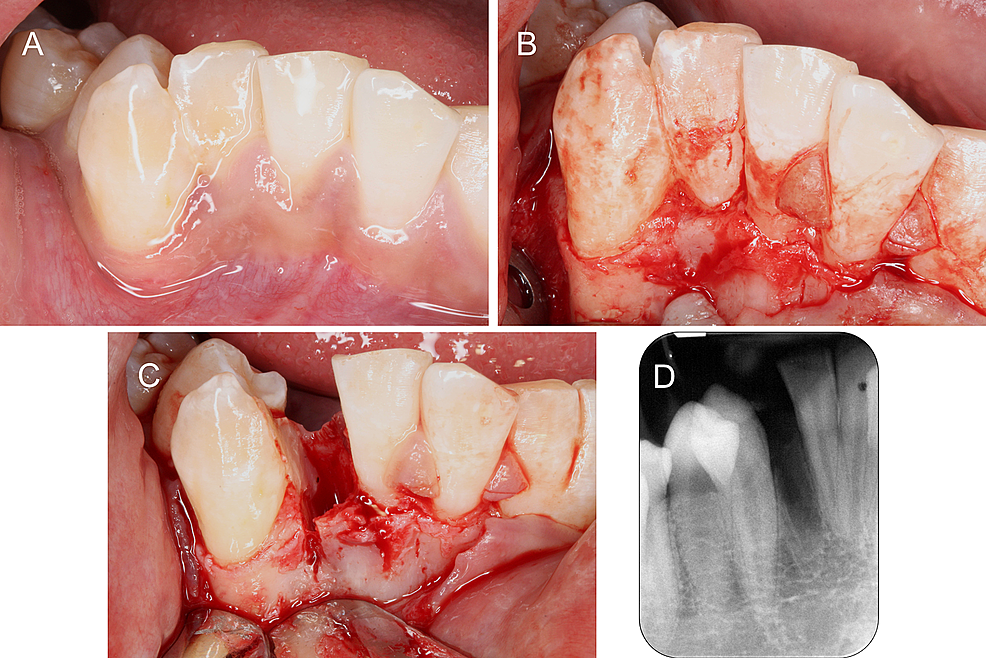

Representative intraoral photos of the fused tooth during root canal... Download Scientific Define Fused Teeth tooth fusion is when two tooth buds fuse together to make one large wide crown. tooth fusion is defined as the union between two or more separate developing teeth. fusion is the conjoining of two adjacent tooth germs, resulting in the formation of a single larger tooth. fusion is the union of two embryologically separate developing. Define Fused Teeth.